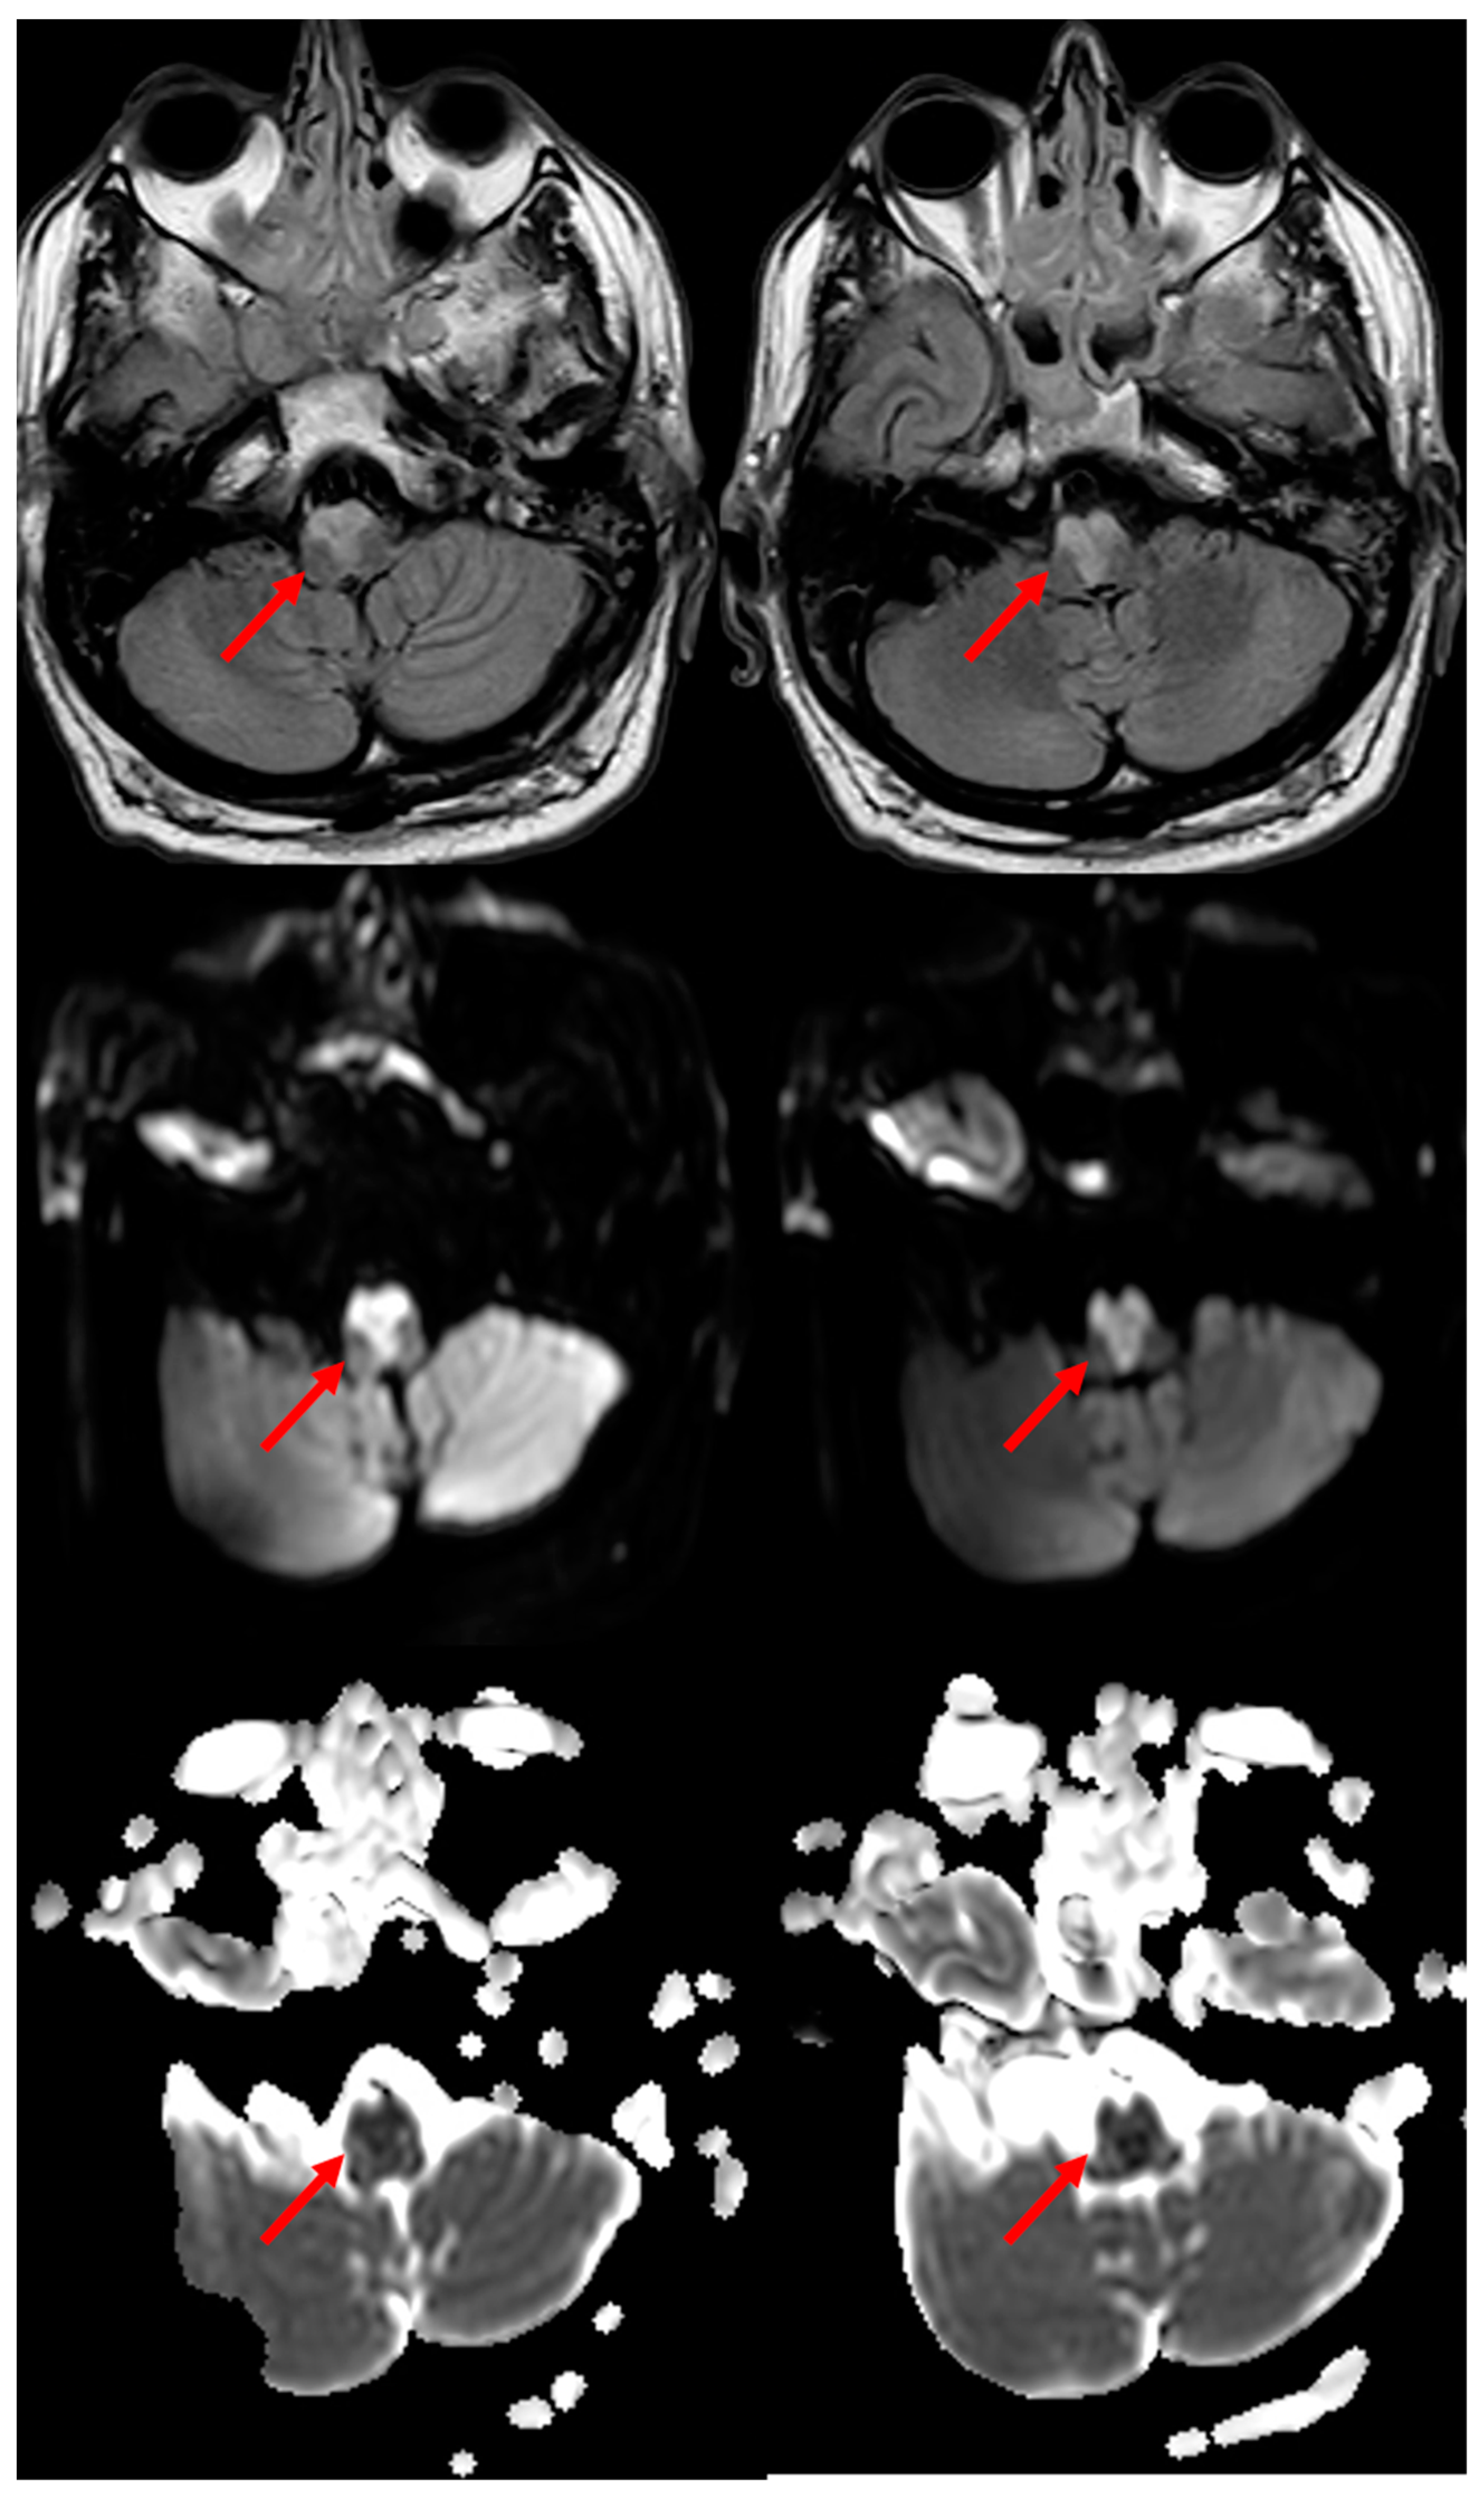

3.1. Medullary Infarction

- Loher, T.J.; Bassetti, C.L.; Stepper, F.P.; Sturzenegger, M.; Kiefer, C.; Nedeltchev, K.; Arnold, M.; Remonda, L.; Schroth, G.; Lovblad, K.-O. Diffusion-weighted MRI in acute spinal cord ischaemia. Neuroradiology 2003, 45, 557–561. [Google Scholar] [CrossRef]

- Thurnher, M.M.; Bammer, R. Diffusion-weighted MR imaging (DWI) in spinal cord ischemia. Neuroradiology 2006, 48, 795–801. [Google Scholar] [CrossRef]

- Küker, W.; Weller, M.; Klose, U.; Krapf, H.; Dichgans, J.; Nägele, T. Diffusion-weighted MRI of spinal cord infarction—High resolution imaging and time course of diffusion abnormality. J. Neurol. 2004, 251, 818–824. [Google Scholar] [CrossRef]

- Vargas, M.I.; Gariani, J.; Sztajzel, R.; Barnaure-Nachbar, I.; Delattre, B.M.; Lovblad, K.O.; Dietemann, J.L. Spinal Cord Ischemia: Practical Imaging Tips, Pearls, and Pitfalls. AJNR Am. J. Neuroradiol. 2015, 36, 825–830. [Google Scholar] [CrossRef]